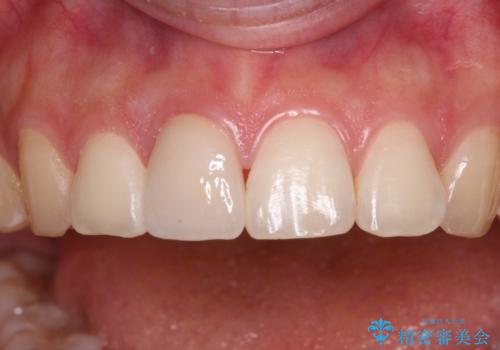

転んで前歯の先端1/3ほどが欠けており、近医にて応急処置としてコンポジットレジン修復がされていました。

審美性や舌触り、今後の歯への負担などを考え、オールセラミッククラウンにて補綴治療を行うこととしました。